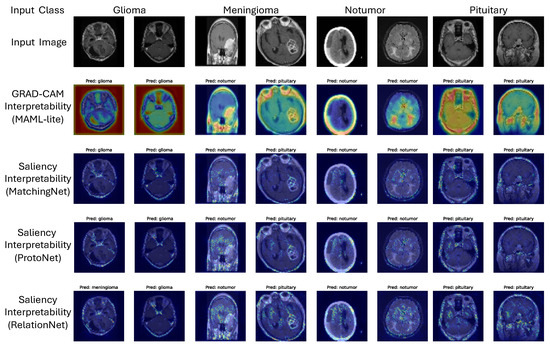

3.6.2. Few-Shot Learning Models

MAML-lite Grad-CAM results (Figure 9) reveal strong attention to tumor regions in correctly classified glioma images, but in some “no tumor” cases, activations shifted toward the pituitary region, explaining observed confusion. MatchingNet saliency maps occasionally emphasized background structures, contributing to errors in meningioma cases (Figure 9). ProtoNet saliency visualizations highlighted correct tumor regions in glioma but sometimes misfocused on meningioma areas, leading to cross-class misclassifications (Figure 9).

Overall, these analyses provide direct visual evidence of the models’ strengths and limitations. In particular, they confirm that dataset reduction (10% scenario) amplifies confusion between “no tumor” and “pituitary tumor” due to overlapping activation regions.

To address interpretability concerns, we incorporated visual explanations of how models make predictions. Specifically, we generated Grad-CAM maps for CNN, ResNet, and MAML-lite, and saliency maps for LSTM, MatchingNet, and ProtoNet. These heatmaps illustrate the image regions that contributed most to the model’s decision for each class (glioma, meningioma, pituitary tumor, and no tumor). For glioma and meningioma, CNN and ResNet heatmaps consistently highlighted tumor boundaries, validating that the models rely on clinically relevant regions. For no-tumor cases misclassified as pituitary tumor (under 10% dataset), both CNN and MAML-lite heatmaps showed strong activation in the pituitary region, explaining the confusion. LSTM saliency maps revealed broader distributed activations, while MatchingNet occasionally focused on background textures, leading to errors in meningioma classification. ProtoNet showed reasonable localization but sometimes confused glioma and meningioma boundaries when they overlapped anatomically. Representative examples are shown in Figure 8 and Figure 9, where heatmaps are overlaid on MRI slices to enhance clinical interpretability.

Figure 9. Interpretability for few-shot models: Grad-CAM (MAML-lite) and saliency (MatchingNet, ProtoNet, RelationNet) reveal tumor-focused attention on correct cases and background/pituitary activation on specific errors, clarifying cross-class confusions. Warmer colors (red/yellow) indicate regions with higher contribution to the predicted class, while cooler colors (blue) indicate lower contribution.